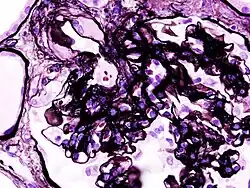

Las glomerulonefritis secundarias mantienen el mismo patrón histológico que las causas primarias aunque guardan características que las diferencian:[2]

- Nefropatía diabética: se trata de una complicación que se da en algunos diabéticos. El exceso de glucosa en sangre termina acumulándose en las estructuras renales produciendo que se inflamen y no puedan cumplir correctamente su función. Esto conlleva la filtración de proteínas en la orina.